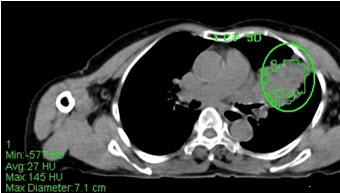

Hình 4. Bệnh nhân Nguyễn T.V., nữ, 72 tuổi. Chẩn đoán: U lympho ác tính không Hodgkin biểu hiện tại phổi, giải phẫu bệnh là: WF6. Hình CT và PET/CT cho thấy khối u phổi trái tăng hấp thu FDG (trong vòng tròn) với max SUV=7,94.